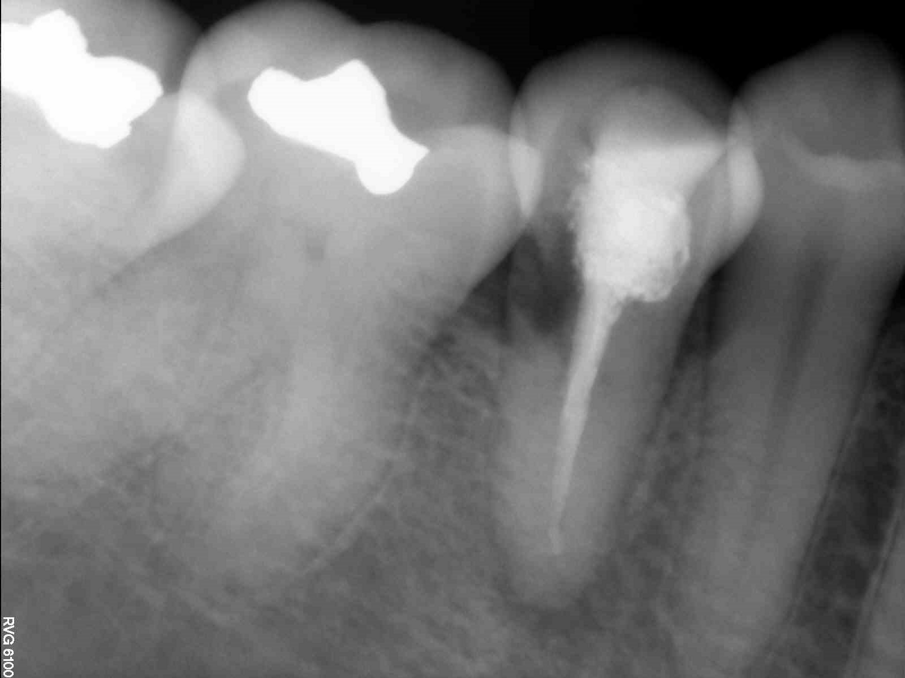

L’esame radiografico ha mostrato radiolucenza periapicale e una lesione radiolucente nella zona cervicale del dente (Figg. 1, 2). Per determinare l’estensione e la profondità della lesione, è stata eseguita una scansione CBCT (Figg. 3a-3d). Sulla base delle immagini CBCT e delle ricostruzioni 3D, è stata individuata una diagnosi di riassorbimento invasivo extracanalare (ECIR) di classe III di Heithersay in un dente trattato endodonticamente con parodontite apicale sintomatica. Il paziente è stato informato della diagnosi, delle alternative del piano di trattamento e della prognosi del caso. L’ECIR è una forma di riassorbimento della radice cervicale esterna e rappresenta ancora un enigma per gli endodontisti per quanto riguarda la sua natura e le sue cause. In questa circostanza, potrebbe essere stato dovuto dalle forze generate dal trattamento ortodontico o da precedenti trattamenti parodontali, poiché il dente 45 era stato precedentemente diagnosticato con parodontite cronica sintomatica. Il difetto di riassorbimento causato dall’ECIR viene trattato, come proposto da Heithersay, utilizzando una nuova alternativa terapeutica, quale l’estrusione chirurgica intenzionale e la chirurgia periapicale1. Heithersay ha classificato l’ECIR in quattro tipi clinici. Nella classe I e II, la percentuale di successo del trattamento è generalmente del 100%, ma la percentuale di successo del trattamento scende al 77% nella classe III e al 12% nella classe IV. Quanto più avanzato è il riassorbimento, tanto peggiore è la prognosi e tanto più complesso il trattamento1.

Fig. 1 - Radiografia panoramica della situazione iniziale.

Fig. 2 - Radiografia periapicale della situazione iniziale. (Tutte le immagini: © Dr. Johnny Onori).